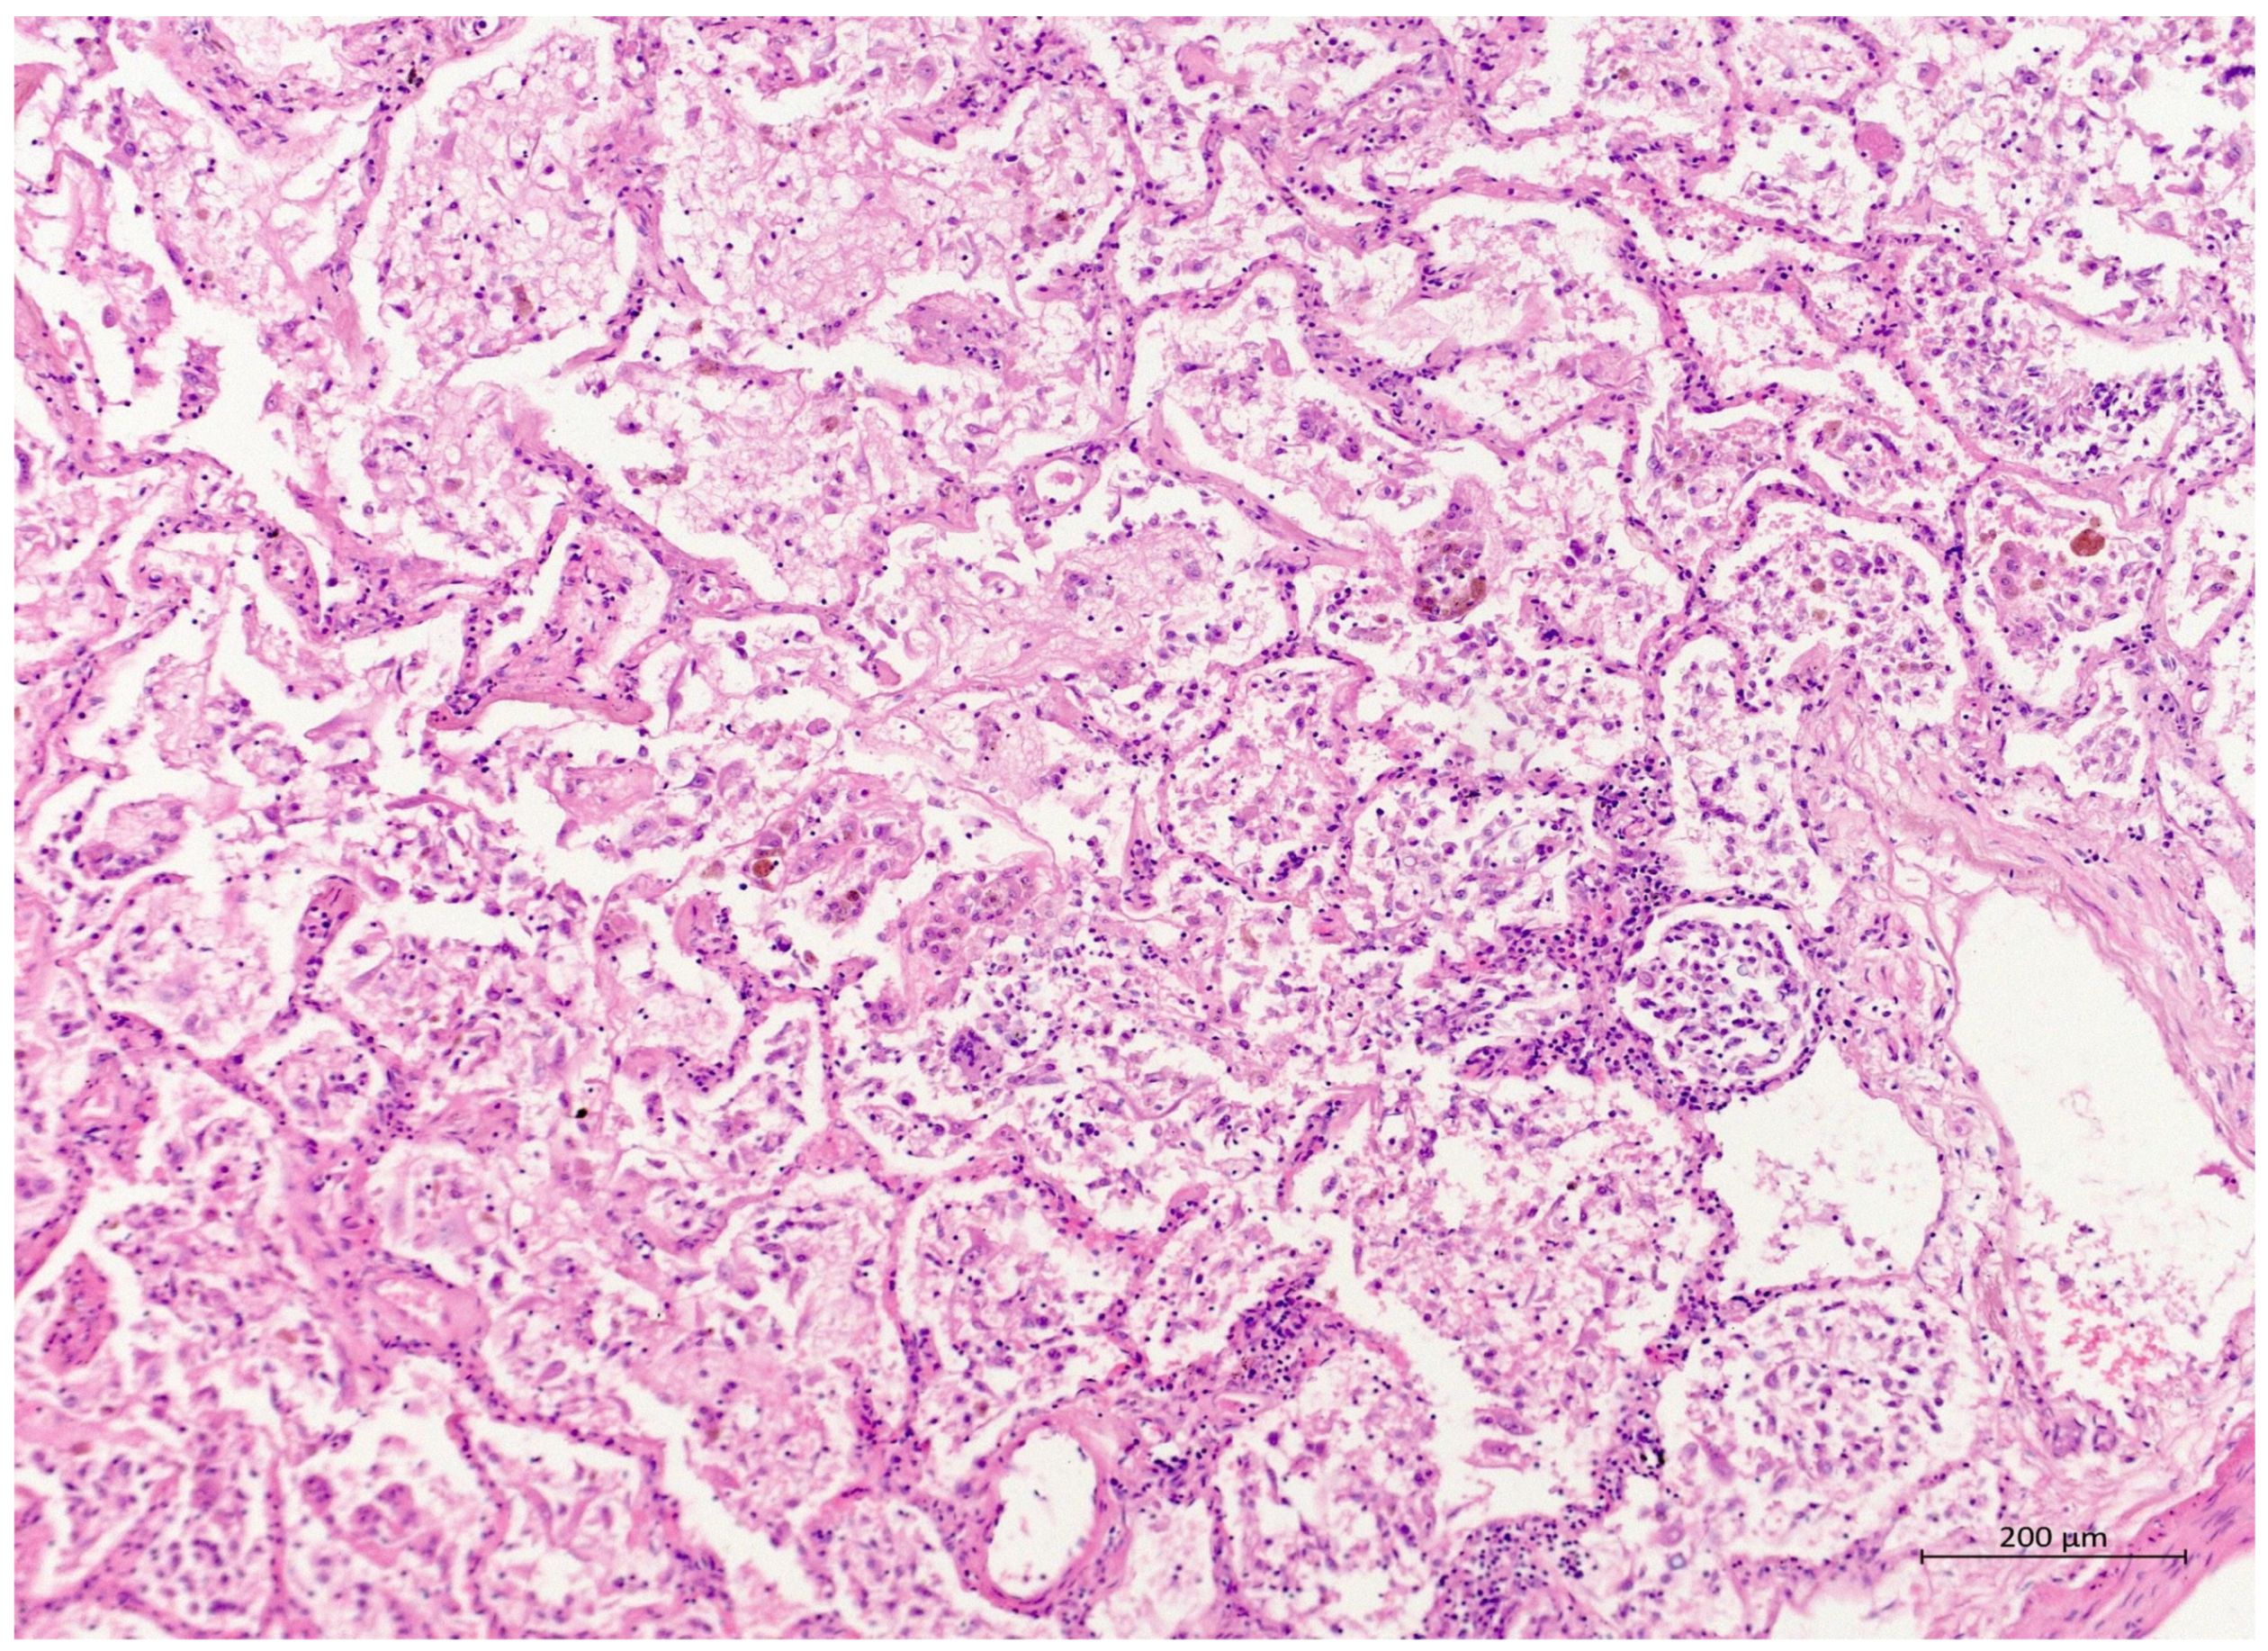

Figure 2.

(H&E, 10×) H&E staining showing lung parenchyma with alveoli filled with exudated foamy fluid, hyaline membrane remnants, numerous desquamated cells, and mixed inflammatory infiltrate. The proliferation of myofibroblasts can be seen sporadically. The interalveolar septa were somewhat thickened.

A 60 year old male smoker with a history of arterial hypertension and myocardial infarction developed typical COVID-19 symptoms in April 2021—cough, exertional dyspnoea, chest tightness, and fever. Developing prior to the widespread availability of antiCOVID-19 vaccines, he was unvaccinated. Four days after the onset of symptoms, he was admitted to the Pulmonary Department of the University Hospital Brno due to the worsening dyspnoea. He tested positive for SARS-CoV-2. The exact viral variant was not identified. The predominant variant in the Czech population was B.1.1.7 (Alpha) at that time. His initial chest X-ray revealed diffuse lung infiltrates, especially in the right upper-middle quadrant. Despite receiving standard treatment with remdesivir for five days, corticosteroids (methylprednisolone 80 mg intravenously per day), and a prophylactic dose of low-molecular-weight heparin (LMWH), his dyspnoea worsened. Hence, supplemental oxygen and antibiotics (i.e., clarithromycin 500 mg IV BID and ceftriaxone 2 g IV BID for 5 days) were administered. Due to the progressively increasing levels of D-Dimers in laboratory tests, CT angiography was performed, showing typical findings consistent with COVID-19 pneumonia of diffuse lung parenchyma involvement without any signs of pulmonary embolism (Figure 1). The patient’s oxygen was gradually increased to achieve a peripheral blood saturation of >90%. On day 11, the patient was transferred to the ICU after his saturation dropped to 50–60% despite an oxygen flow via face mask of approximately 15 litres per minute. High-flow oxygen therapy (HFOT) with awake prone positioning was commenced, and corticosteroids were switched from methylprednisolone 80 mg to dexamethasone 6 mg IV per day. Despite ten days of corticosteroid administration, the patient’s clinical condition began to deteriorate significantly, and his hypoxaemia worsened. On day 12, he was intubated and placed on invasive ventilation with aggressive parameters (positive end-expiratory pressure: 12 cm H2O; fraction of oxygen: 80%). Bronchoalveolar lavage (BAL) was performed with the PCR testing showing more than 2 million copies of SARS-CoV-2 per millilitre (a significant number); no fungal DNA was detected at this time. As the patient became anuric, daily dialysis treatment commenced on day 13. Ventilator-associated pneumonia (VAP) caused by Klebsiella pneumoniae producing extended-spectrum beta-lactamase (ESBL) was confirmed by BAL fluid cultivation, and meropenem 2 g per day in continuous infusion was started. Serum levels of cardiac markers were elevated (troponin T: 67 ng/L; NT pro Brain Natriuretic Peptide (NTproBNP): 3892 ng/L), indicating advancing myocardial injury. Norepinephrine infusion was needed to achieve adequate blood pressure. The capillary refill time was prolonged over 2 s, consistent with circulatory dysfunction. A day later, the patient developed atrial fibrillation and hemodynamic instability with doses of norepinephrine up to 0.5 µg/kg/min. On day 16, a tracheostomy was performed, while the ventilation remained fully controlled with a P/F (PaO2/inspiration fraction of O2) index below 150. Two days later, the progression of circulatory dysfunction became apparent, accompanied by an elevation of inflammatory markers. Follow-up BAL was performed, empirical vancomycin was added on day 19, and doses were adjusted respecting dialysis procedures. Abdominal ultrasound revealed no clear site of a new infection. Blood cultures were negative, and BAL showed more than 3 million copies of SARS-CoV-2 and 1200 copies of Cryptococcus neoformans per millilitre/BAL. Serum panfungal antigen ((1,3)-β-glucan D) and serum cryptococcal antigen (i.e., glucuronoxylomannan) levels were negative. Over the next four days, organ dysfunction slightly improved; therefore, the patient was slowly weaned-off sedation, and the mode of ventilation was switched to pressure support. On day 21, vancomycin was switched to linezolid 600 mg IV BID. On day 22, a follow-up BAL was performed. PCR showed borderline positivity for Cryptococcus neoformans (300 copies per millilitre), and serum positivity for cryptococcal antigen was detected. Combined antifungal therapy with liposomal amphotericin B (Abelcet) 500 mg IV per day and fluconazole 800 mg IV per day was commenced. Blood cultures were negative for bacteria and fungi. Cerebrospinal fluid analysis, including PCR, ruled out CNS dissemination. On day 24, the patient’s circulatory instability progressed rapidly with no response to vasopressors and inotropes, which led to a subsequent cardiac arrest followed by unsuccessful cardiopulmonary resuscitation (CPR). Multiorgan dysfunction caused by COVID-19 infection and cryptococcal pneumonia was stated as the primary cause of death from a clinician’s perspective. The most significant feature during the histopathological examination was the severe diffuse alveolar damage (DAD) (Figure 2), specifically its exudative/proliferative stage, due to the prolonged period of COVID-19 pneumonia. In addition, a considerable number of dispersed intra-alveolar microorganisms, with a thick mucus capsule, were found in the lung parenchyma (Figure 3). These microorganisms (variably sized: approximately 7–20 μm) stained with both Alcian blue (Figure 4) and Giemsa (Figure 5). There was only a very subtle inflammatory reaction in the surrounding tissue, mostly lymphocytic. A post-mortem lung smear was microbiologically tested and returned positive for Cryptococcus neoformans. Thus, we consider secondary lung cryptococcosis as proven. Respiratory failure as a result of DAD was the immediate cause of death of the patient.